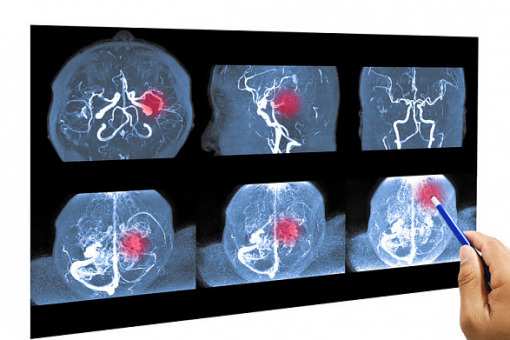

Ważne doniesienia z tegorocznego kongresu Europejskiej Organizacji Udarowej (European Stroke Organisation Conference – ESOC) – udowodniono skuteczność terapii endowaskularnej u pacjentów z udarem niedokrwiennym w obrębie tętnicy podstawnej mózgu.

Udar ten reprezentuje od 1 proc. do 4 proc. wszystkich udarów niedokrwiennych. Niebezpieczeństwo tego typu niedokrwienia polega na tym, że jego objawy mogą naśladować inne stany, powodując opóźnienie w ocenie neurologicznej – a czas jest tu najcenniejszy.